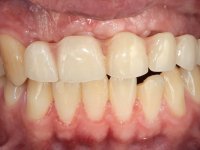

Male patient, 22 years old, non-smoker, appear in our dental office 6 months after a car accident where he lost teeth 21, 22, 23 and 24. Teeth 12 and 11 present mobility grade III, thus with a prognosis of extraction. The gengiva architecture of the edentulous area presents a recession and a flat surface.

TREATMENT NOTES:

The diagnostic wax-up enclose the possibility to include, or not, gum-shade ceramics to rehabilitate the interdental papillae. This two possibilities were presented to the patient due to the bone regeneration unpredictability (in our opinion), mainly vertically.